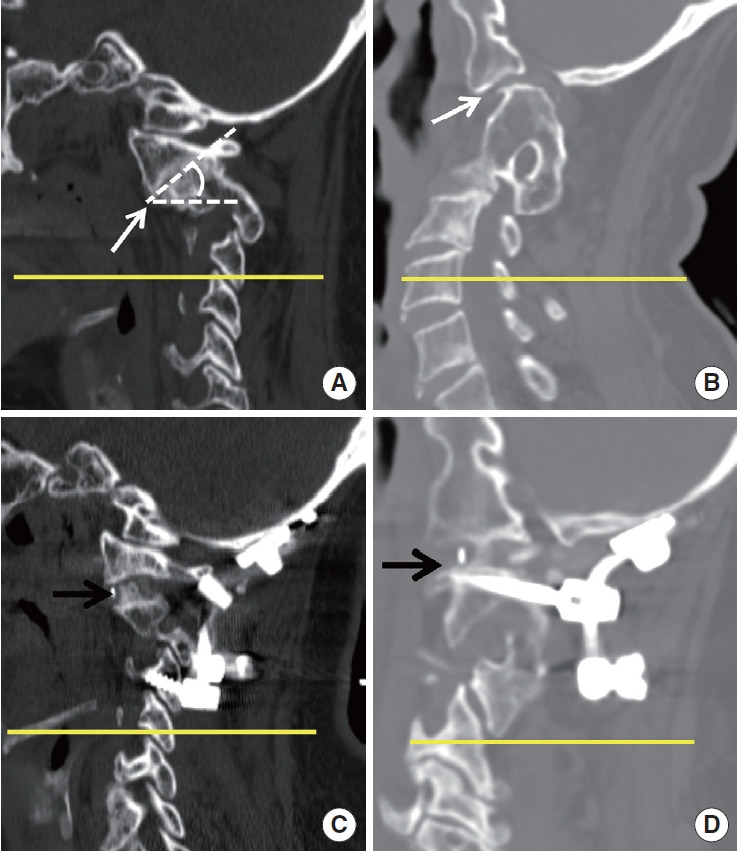

Methods: A retrospective analysis was performed on 28 patients who underwent craniocervical realignment between 2014 and 2022 for CVJ kyphosis with accompanying negative sagittal imbalance. Clinical outcomes were evaluated using the Neck Disability Index (NDI), visual analogue scale for neck pain, and the Japanese Orthopaedic Association (JOA) score. Radiographic parameters included the C0-2 angle and the C2-7 sagittal vertical axis (SVA). Favorable outcomes were defined as an improvement of more than 20 points in the NDI and a JOA recovery rate exceeding 50%. Multiple linear regression and receiver operating characteristic (ROC) curve analyses were conducted to identify independent predictors and to determine optimal threshold values.

Results: Significant improvements in both clinical outcomes and radiographic alignment were observed in association with craniocervical realignment surgery. Patients who achieved favorable outcomes exhibited greater postoperative changes in the C0-2 angle and the C2-7 SVA. Multivariate analysis identified changesm in the C0-2 angle (p=0.019) and C2-7 SVA (p=0.010) as independent predictors of NDI improvement, while age (p=0.033) and C2-7 SVA change (p=0.037) were independently associated with the JOA recovery rate. ROC curve analysis determined optimal cutoff values of ≥10.65° for C0-2 angle change and ≥19.2 mm for C2-7 SVA change, with corresponding area under the curve values of 0.872 and 0.802, respectively.

Conclusion: Craniocervical realignment appears to be a viable surgical option for patients with CVJ kyphosis and negative sagittal imbalance. Postoperative changes in C0-2 angle and C2-7 SVA were found to be associated with favorable clinical and functional outcomes, suggesting their potential role as prognostic factors.